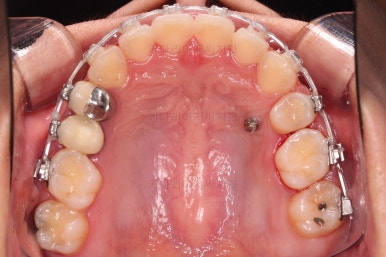

우선 장치를 부착했습니다.

이번에 선택한 장치는 엠파워 클리어라고 하는 자가결찰 세라믹 장치인데요.

흔히 아시는 클리피씨 장치와 같은 분류의 장치입니다. 클리피는 일본, 엠파워는 미국 제조사라는 차이가 있지만 큰 틀에서는 세라믹 바디에 금속 클립이 달린 거의 동일한 장치라고 보시면 됩니다.

장치 부착 직후의 모습인데요.

장치가 보이는 느낌이나 옆라인의 변화 양상은 참고해 주세요.

옆라인은 입이 많이 튀어나오는 분도 있고 거의 변화가 없는 분도 있는데 이 분이 거의 중간 정도 변하시는 느낌입니다.